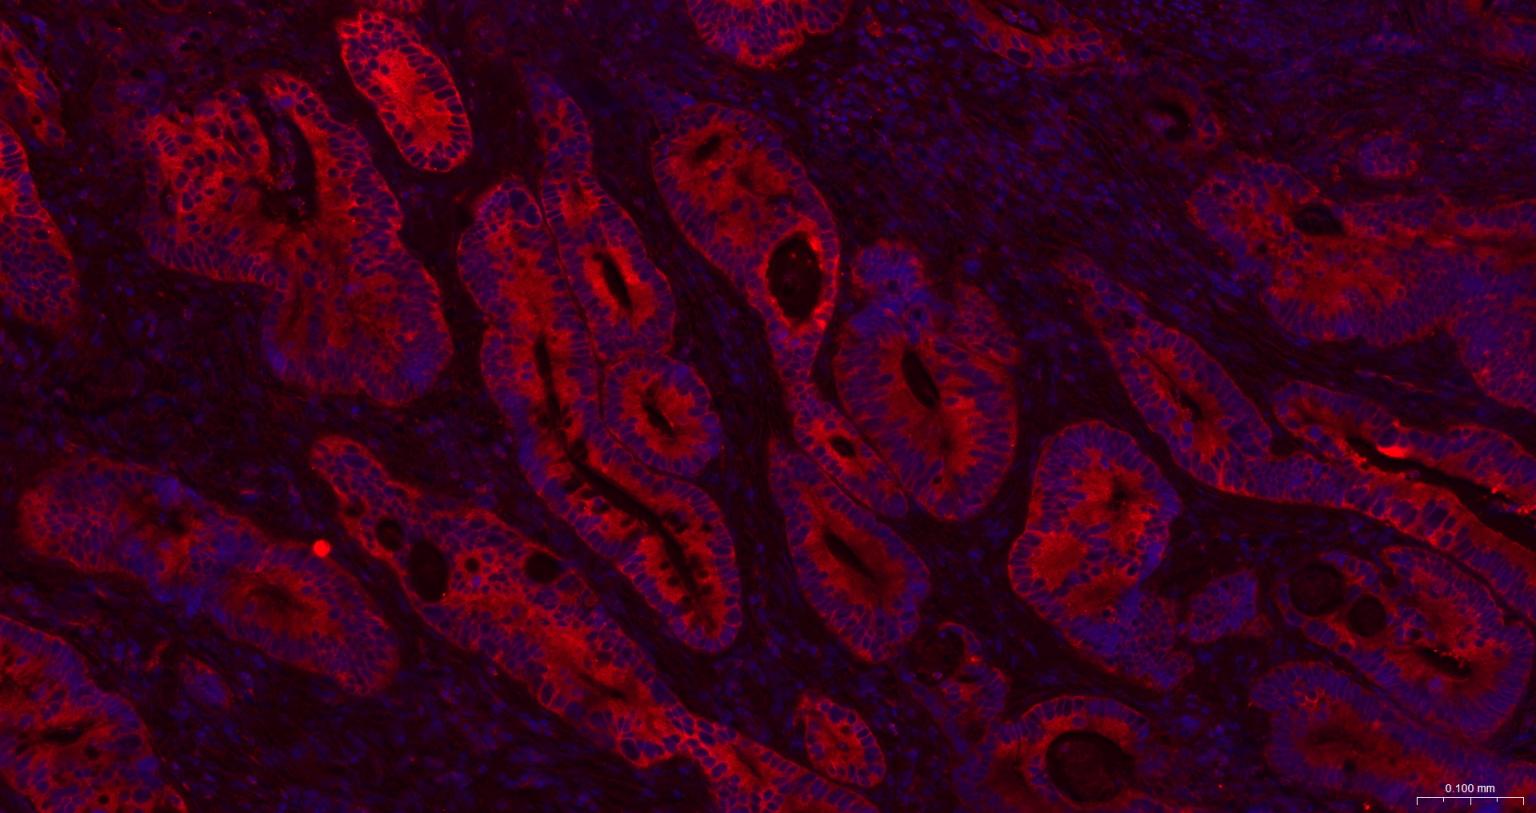

| ICC/IF | Human, Mouse, Rat | 1:50-200 |